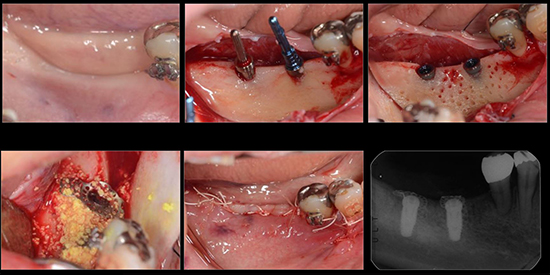

治療中04

治療中05

治療中06